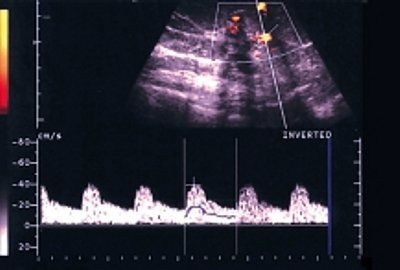

б) Импульсный допплеровский режим. До лечения: опухоль с нечеткими, неровными контурами, неправильной формы, неоднородной структуры, с выраженной васкуляризацией.

б) Импульсный допплеровский режим. До лечения: опухоль с нечеткими, неровными контурами, неоднородной структуры с отражениями пониженной интенсивности, с большим количеством сосудов.